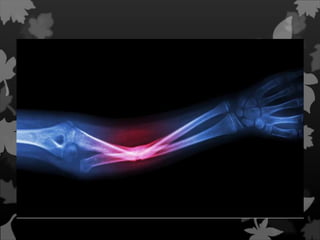

Fratura de Galeazzi

Uma fratura de

Galeazzi é

uma fratura da região

distal do rádio com

ruptura da membrana

interóssea e da

ligação com a ulna,

com subluxação da

ulna.

Fratura de Galeazzi Umafratura de Galeazzi é uma fratura da região distal do rádio com ruptura da membrana interóssea e da ligação com a ulna, com subluxação da ulna.